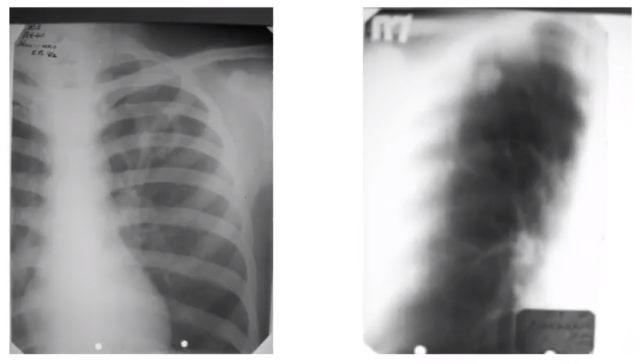

Медицинские аспекты заболеваний: рентгенологическая картина туберкулеза костей

Раздел: Снимки-откровения